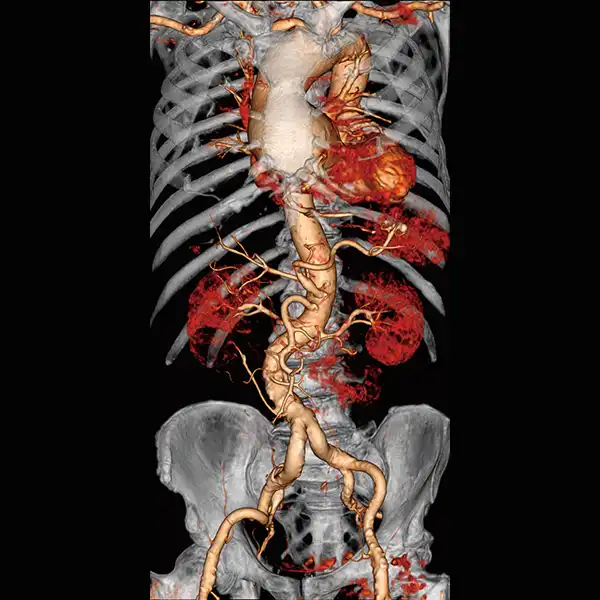

GENESIS Edition’s 16 cm wide area detector signicantly improves your ability to obtain high-quality images for routine and advanced studies. One rotation is all it takes to acquire a whole heart, a neonatal chest, a foot or an ankle exam – in a fraction of a second with less dose and great z-axis uniformity.

Adding dynamic functional imaging to morphology can provide valuable further insights, helping you to optimize disease management and treatment plans. Advanced perfusion maps can assist in diagnosis and therapy response verification of stroke or tumors, while dynamic joint studies help identify causes of pain or immobility.